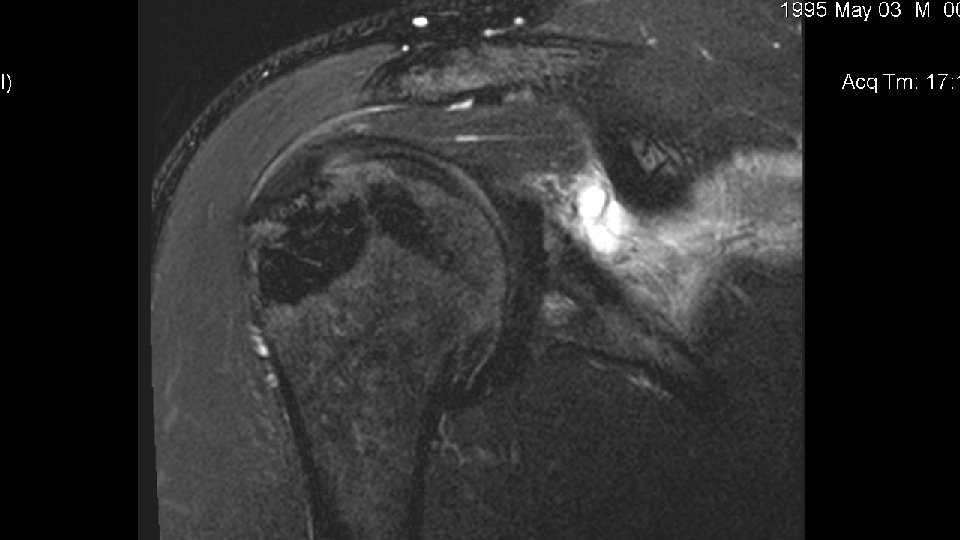

Disposition • The patient was scheduled for MRI